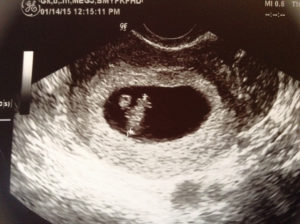

УЗИ

УЗИ на 8 неделе покажет, что ваш малыш такой маленький, с малиновую ягоду, но становится всё больше похожим на крохотного человечка. Малютка уже двигается, шевеля ножками.

Посмотрите на экран УЗИ и увидите как двигается ваш малютка. Если аппаратура достаточно сильная, то она уловит сердцебиение вашего малыша. Сейчас сердечко малютки бьётся быстрее вашего — 150 ударов за минуту.

Сердечные сокращения увидят женщины на экране при УЗИ в 8 недель беременностей.